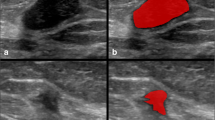

This study investigates the feasibility of using texture radiomics features extracted from mammography images to distinguish between benign and malignant breast lesions and to classify benign lesions into different categories and determine the best machine learning (ML) model to perform the tasks. Six hundred and twenty-two breast lesions from 200 retrospective patient data were segmented and analysed. Three hundred fifty radiomics features were extracted using the Standardized Environment for Radiomics Analysis (SERA) library, one of the radiomics implementations endorsed by the Image Biomarker Standardisation Initiative (IBSI). The radiomics features and selected patient characteristics were used to train selected machine learning models to classify the breast lesions. A fivefold cross-validation was used to evaluate the performance of the ML models and the top 10 most important features were identified. The random forest (RF) ensemble gave the highest accuracy (89.3%) and positive predictive value (66%) and likelihood ratio of 13.5 in categorising benign and malignant lesions. For the classification of benign lesions, the RF model again gave the highest likelihood ratio of 3.4 compared to the other models. Morphological and textural radiomics features were identified as the top 10 most important features from the random forest models. Patient age was also identified as one of the significant features in the RF model. We concluded that machine learning models trained against texture-based radiomics features and patient features give reasonable performance in differentiating benign versus malignant breast lesions. Our study also demonstrated that the radiomics-based machine learning models were able to emulate the visual assessment of mammography lesions, typically used by radiologists, leading to a better understanding of how the machine learning model arrive at their decision.